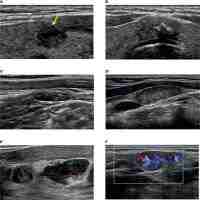

| Abstract | Background Accurate preoperative evaluation for metastatic lesions is significant for PTC patients. However, the stratification systems revealed inconsistencies in the ultrasound (US) features of cervical metastatic lymph nodes (LNs). This study aimed to investigate and develop a risk stratification model based on US radiologic features for cervical metastatic lesions in PTC patients. Methods This study retrospectively enrolled 1806 LNs from 1665 PTC patients who underwent US-guided fine-needle aspiration biopsy for cervical LNs from January 2010 to December 2022. Univariable and multivariable logistic regression analyses determined and developed the independent risk US features and a risk stratification model for cervical metastatic LNs. The performance of the risk stratification model was assessed and validated by the Korean Society of Thyroid Radiology and the European Thyroid Association. Results Among the 1806 LNs, 1411 LNs were pathologically diagnosed with malignant. Multivariate analysis indicated that the absence of fatty hilum, cystic components, round shape (SD/LD ≥ 0.5), abundant vascularity, hyperechogenicity (including hyper and hypo-echogenicity, and hyper-echogenicity), and calcifications (include microcalcification, and macrocalcification) were independent risk US features associated with malignant LNs. A risk stratification model for cervical metastatic LNs was developed based on these suspicious US features and showed well-predicted performance (C-index 0.840; 95% CI: 0.840–0.923). Conclusion Our study proposed a new risk stratification system based on US radiologic features to predict cervical metastatic lymph nodes in PTC patients. We identified several risk factors for lymph node (LN) metastasis from PTC including the absence of fatty hilum, cystic components, round shape (SD/LD ≥ 0.5), abnormal vascularity, hyper-echogenicity, hyper- and hypo-echogenicity, microcalcification, and macrocalcification. These features could serve as valuable indicators for surgeons to accurately assess the status of cervical LNs. |